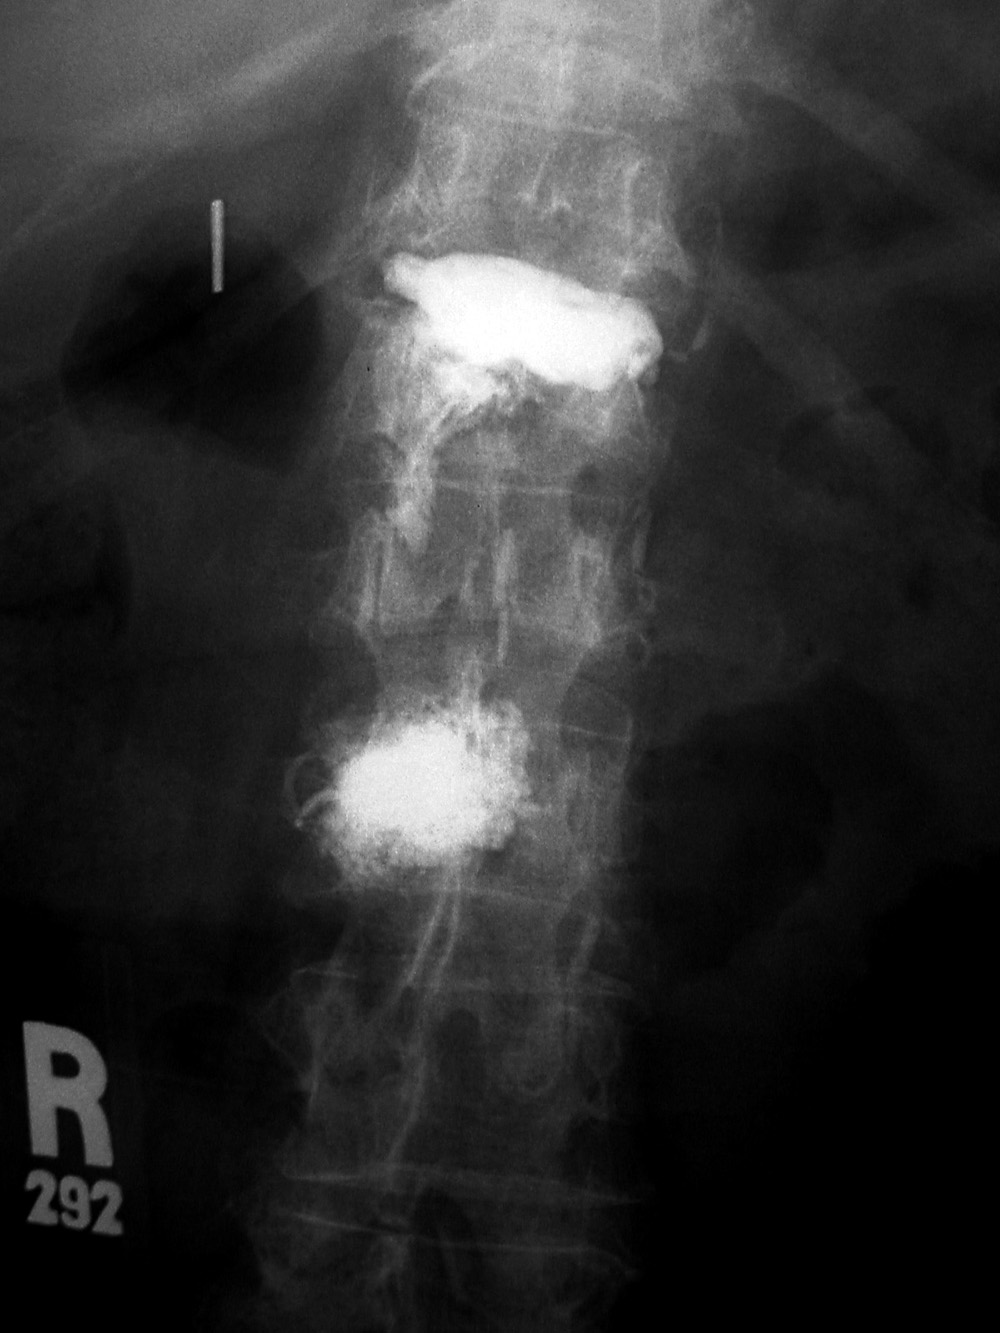

Vertebroplasty is designed to provide pain relief from benign osteoporotic compression fractures or less common, destructive vertebral lesions (Cotten, 1998; Hulme, 2006; Petscavage-Thomas, 2014; McConnell, 2014). Methyl methacrylate is injected directly into a vertebral body to strengthen the bone structure of the vertebra and immobilize fractures, which provides immediate pain relief. If the patients are properly selected and the procedure goes well, vertebroplasty is a dramatic technique. Patients who are bedridden or wheelchair bound have such relief from the chronic

pain of vertebral collapse that they frequently ask to walk out of the hospital. Vertebroplasty is a

serious procedure, and patients must be carefully selected. Because the methyl methacrylate is

mixed with barium sulfate, it is visible on radiographs and on cross-sectional images (figure: vertebroplasty).

Studies in 2009 (Kallmes; Buchbinder) suggested there is little or no benefit of vertebroplasty relative to a control procedure in short term patient reported outcomes, and the use of vertebroplasty has become somewhat controversial. A more recent study with patient reported outcomes through year 1 shows vertebroplasty may provide a modest reduction in pain one year later compared to a control procedure (Comstock, 2013). A 2020 Radiology meta-analysis (Hinde, 2020) suggests vertebroplasty not only improves the quality of life for patients but also helps patients live longer. Further studies are warranted to determine which patients would benefit the most from vertebroplasty (Jennings, 2020).

| Vertebroplasty at L1 and L3 (AP view) |

Vertebroplasty at L1 and L3 (lateral view) |